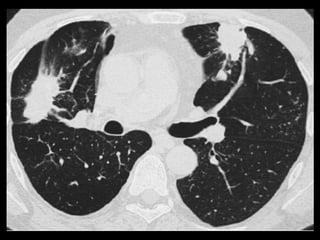

Aspergilose broncopulmonar

invasiva

Radiografias: múltiplos nódulos periféricos, mal

definidos que medem de 1 a 3 cm de tamanho e

gradualmente coalescem em massas maiores ou

áreas de consolidação.

Um achado precoce na TC é a borda de opacidade

em vidro fosco que circunda nódulos(sinal do halo

na TC): o halo representa hemorragia ao redor de

uma área focal de infarto pulmonar causado pelo

Aspergillus, que invade os vasos pulmonares.

Halo: outras infecções, TB, mucormicose, MTX

hemorrágica e Wegener.

Aspergilose broncopulmonar invasiva Radiografias: múltiplos nódulos periféricos, mal definidos que medem de 1 a 3 cm de tamanho e gradualmente coalescem em massas maiores ou áreas de consolidação. Um achado precoce na TC é a borda de opacidade em vidro fosco que circunda nódulos(sinal do halo na TC): o halo representa hemorragia ao redor de uma área focal de infarto pulmonar causado pelo Aspergillus, que invade os vasos pulmonares. Halo: outras infecções, TB, mucormicose, MTX hemorrágica e Wegener.